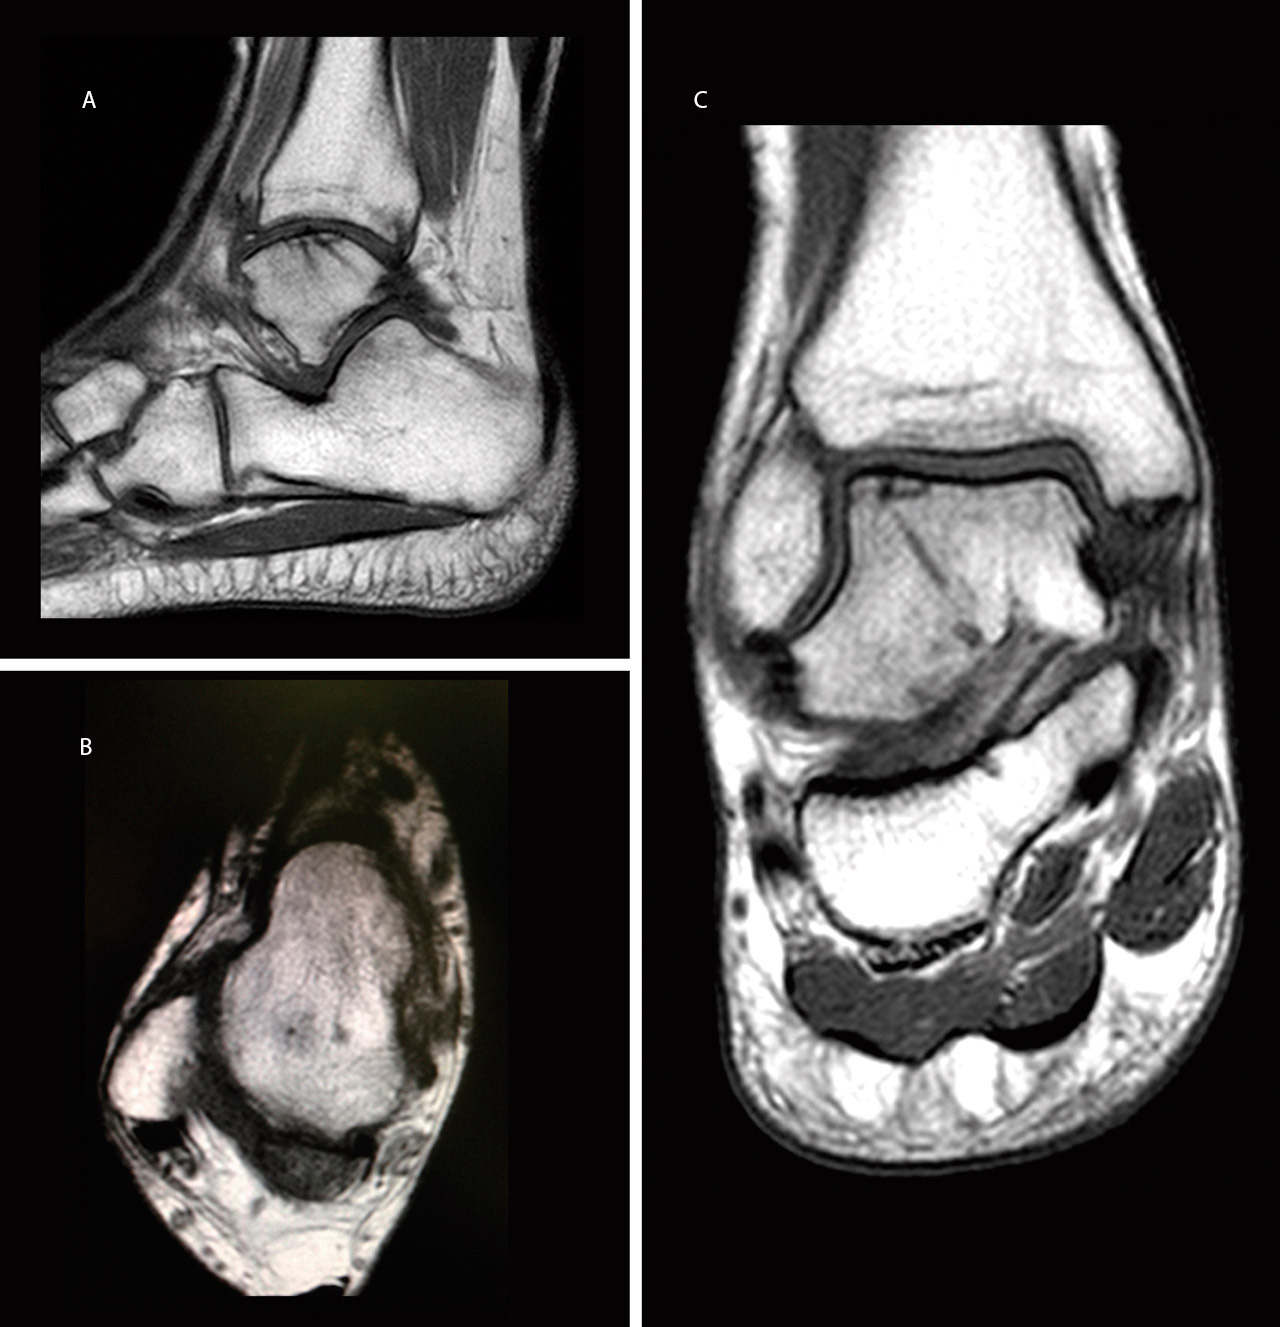

El paciente se reincorporó a su actividad laboral (mozo de almacén) y deportiva a los 4 meses del accidente, sin dolor ni inestabilidad y con un rango de movilidad completo del tobillo. A los 6 meses se realizó una resonancia magnética (RM) que mostró la integración del fragmento, sin escalón articular ni signos de inestabilidad (Figura 3).